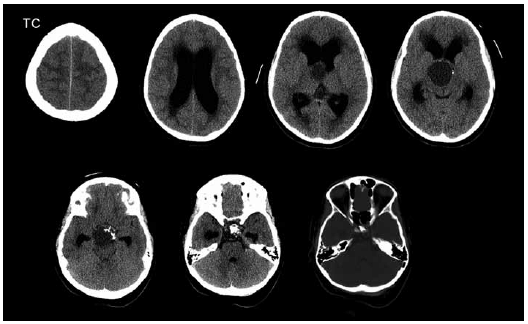

Considere o caso e a imagem a seguir.

Paciente com cefaleia há três semanas. Procurou atendimento anteriormente, mas foi medicado e liberado. Piorou com tonturas e sensação de desmaio e voltou ao pronto-socorro, onde realizaram uma tomografia do crânio.

Em face do exemplo, o diagnóstico é:

Provas